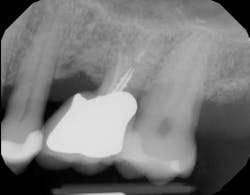

The prognosis is good for molar teeth treated with root amputation, provided case selection and treatment are performed properly. Fugazzottoreported 15-year cumulative success rates comparing molar root resection to molar implant placement, with survival rates of 96.8% for root-resected molars and 97.0% for molar implants.10 This study was done in private practice with proper oversight and case selection.Conclusion

Root amputation remains a viable treatment to save maxillary molars and can have long-term success rates equal to dental implant therapy (figures 9 and 10).Editor’s note: This article originally appeared in Perio-Implant Advisory, a chairside resource for dentists and hygienists that focuses on periodontal- and implant-related issues. Read more articles and subscribe to the newsletter.